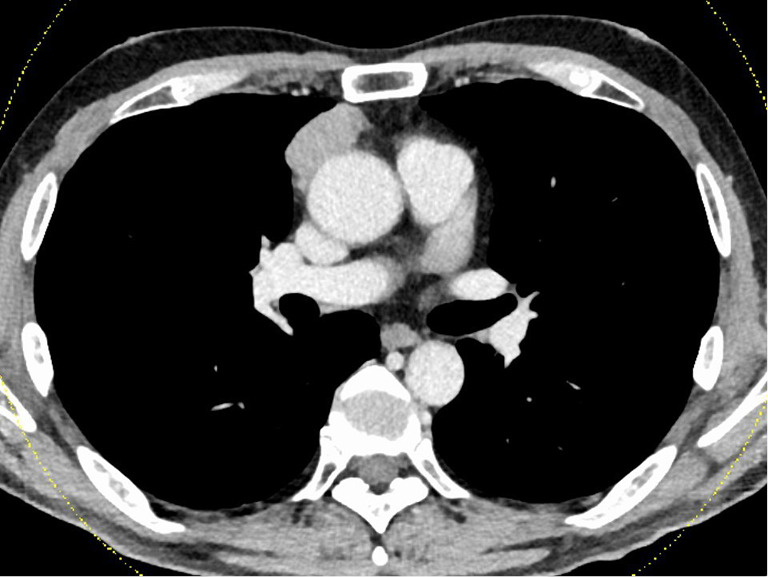

Case description: The first case was a male in his 50s who underwent surgery for Masaoka stage III type B3 thymoma. He experienced a loss of taste before surgery, which showed no improvement after surgery. Due to a MG crisis 44 days after surgery, the patient underwent intensive treatment with mechanical ventilation, steroid pulse therapy, and intravenous immunoglobulin (IVIG) therapy. The patient recovered taste when he started oral food intake after the treatment for the MG crisis (about 3 months after surgery). Despite the recovery of taste after steroid pulse therapy and IVIG therapy, taste disorder gradually worsened about 1 year and 9 months after surgery, resulting in an almost complete loss of sweet taste 2 years after surgery. The second case was a male in his 60s who underwent surgery for Masaoka stage II type B1 thymoma. He experienced loss of taste before surgery, which showed no improvement after surgery. Five years and two months after surgery, the patient was diagnosed with a MG crisis and underwent steroid pulse therapy. Along with improvements in MG symptoms, taste disorders gradually improved. After 6 years and 10 months of surgery, the patient is still alive without MG symptoms (only pyridostigmine, 180 mg/body/day), taste disorder, and thymoma recurrence.

Abstract Image